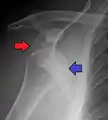

Anterior dislocation of the left shoulder.

A shoulder dislocation often occurs as a result of a fall onto an outstretched arm or onto the shoulder.[3] Diagnosis is typically based on symptoms and confirmed by X-rays.[2] They are classified as anterior, posterior, inferior, and superior with most being anterior.[2][1]